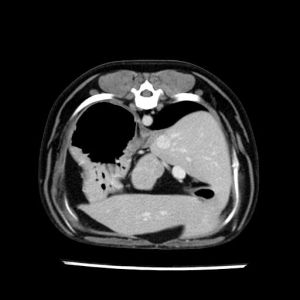

La lesione focale epatica , la ceus,la Tac e il chirurgo .